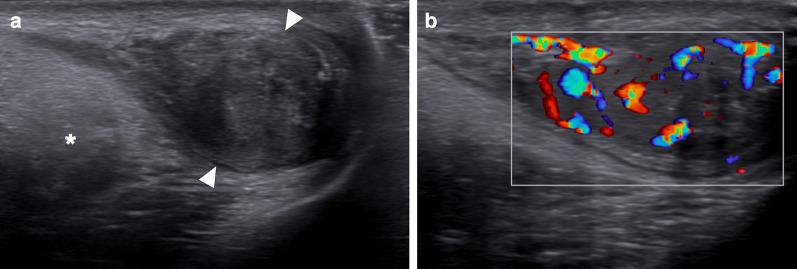

Identifying the deceiver: the non-neoplastic mimickers of genital system neoplasms.

Tumors of the genital system are common and imaging is of crucial importance for their detection and diagnosis. Several non-neoplastic diseases may mimic these tumors and differential diagnosis may be difficult in certain cases. Misdiagnosing non-neoplastic diseases as tumor may prompt unnecessary medical treatment or surgical interventions. In this article, we aimed to present the imaging characteristics of non-neoplastic diseases of the male and female genital systems that may mimic neoplastic processes. Increasing awareness of the imaging specialists to these entities may have a severe positive impact on the management of these patients.